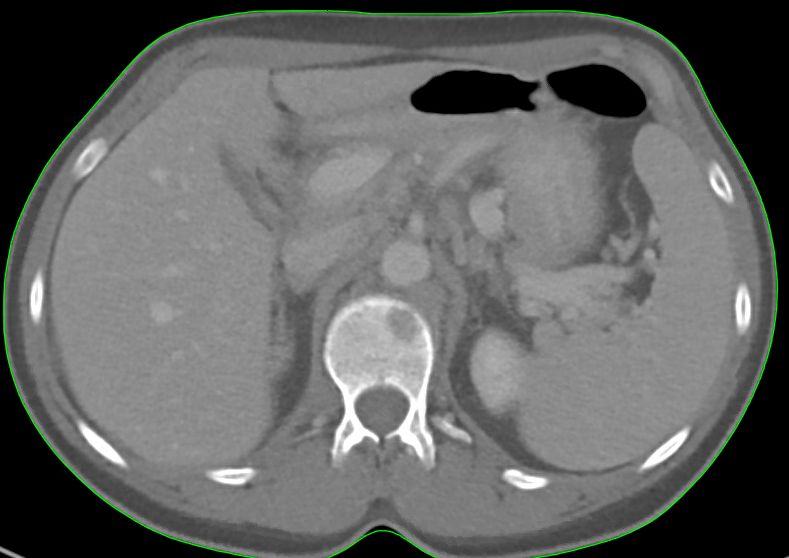

67-jähriger Mann mit primär pulmonal und hepatisch metastasiertem Tumor der rechten Colon-Flexur. Im Nativ-CT Metastasen undeutlich.

CT Kontrastmittel arterielle Phase: Metastasen deutlich.

CT Kontrastmittel venöse Phase: Metastasen sehr deutlich.